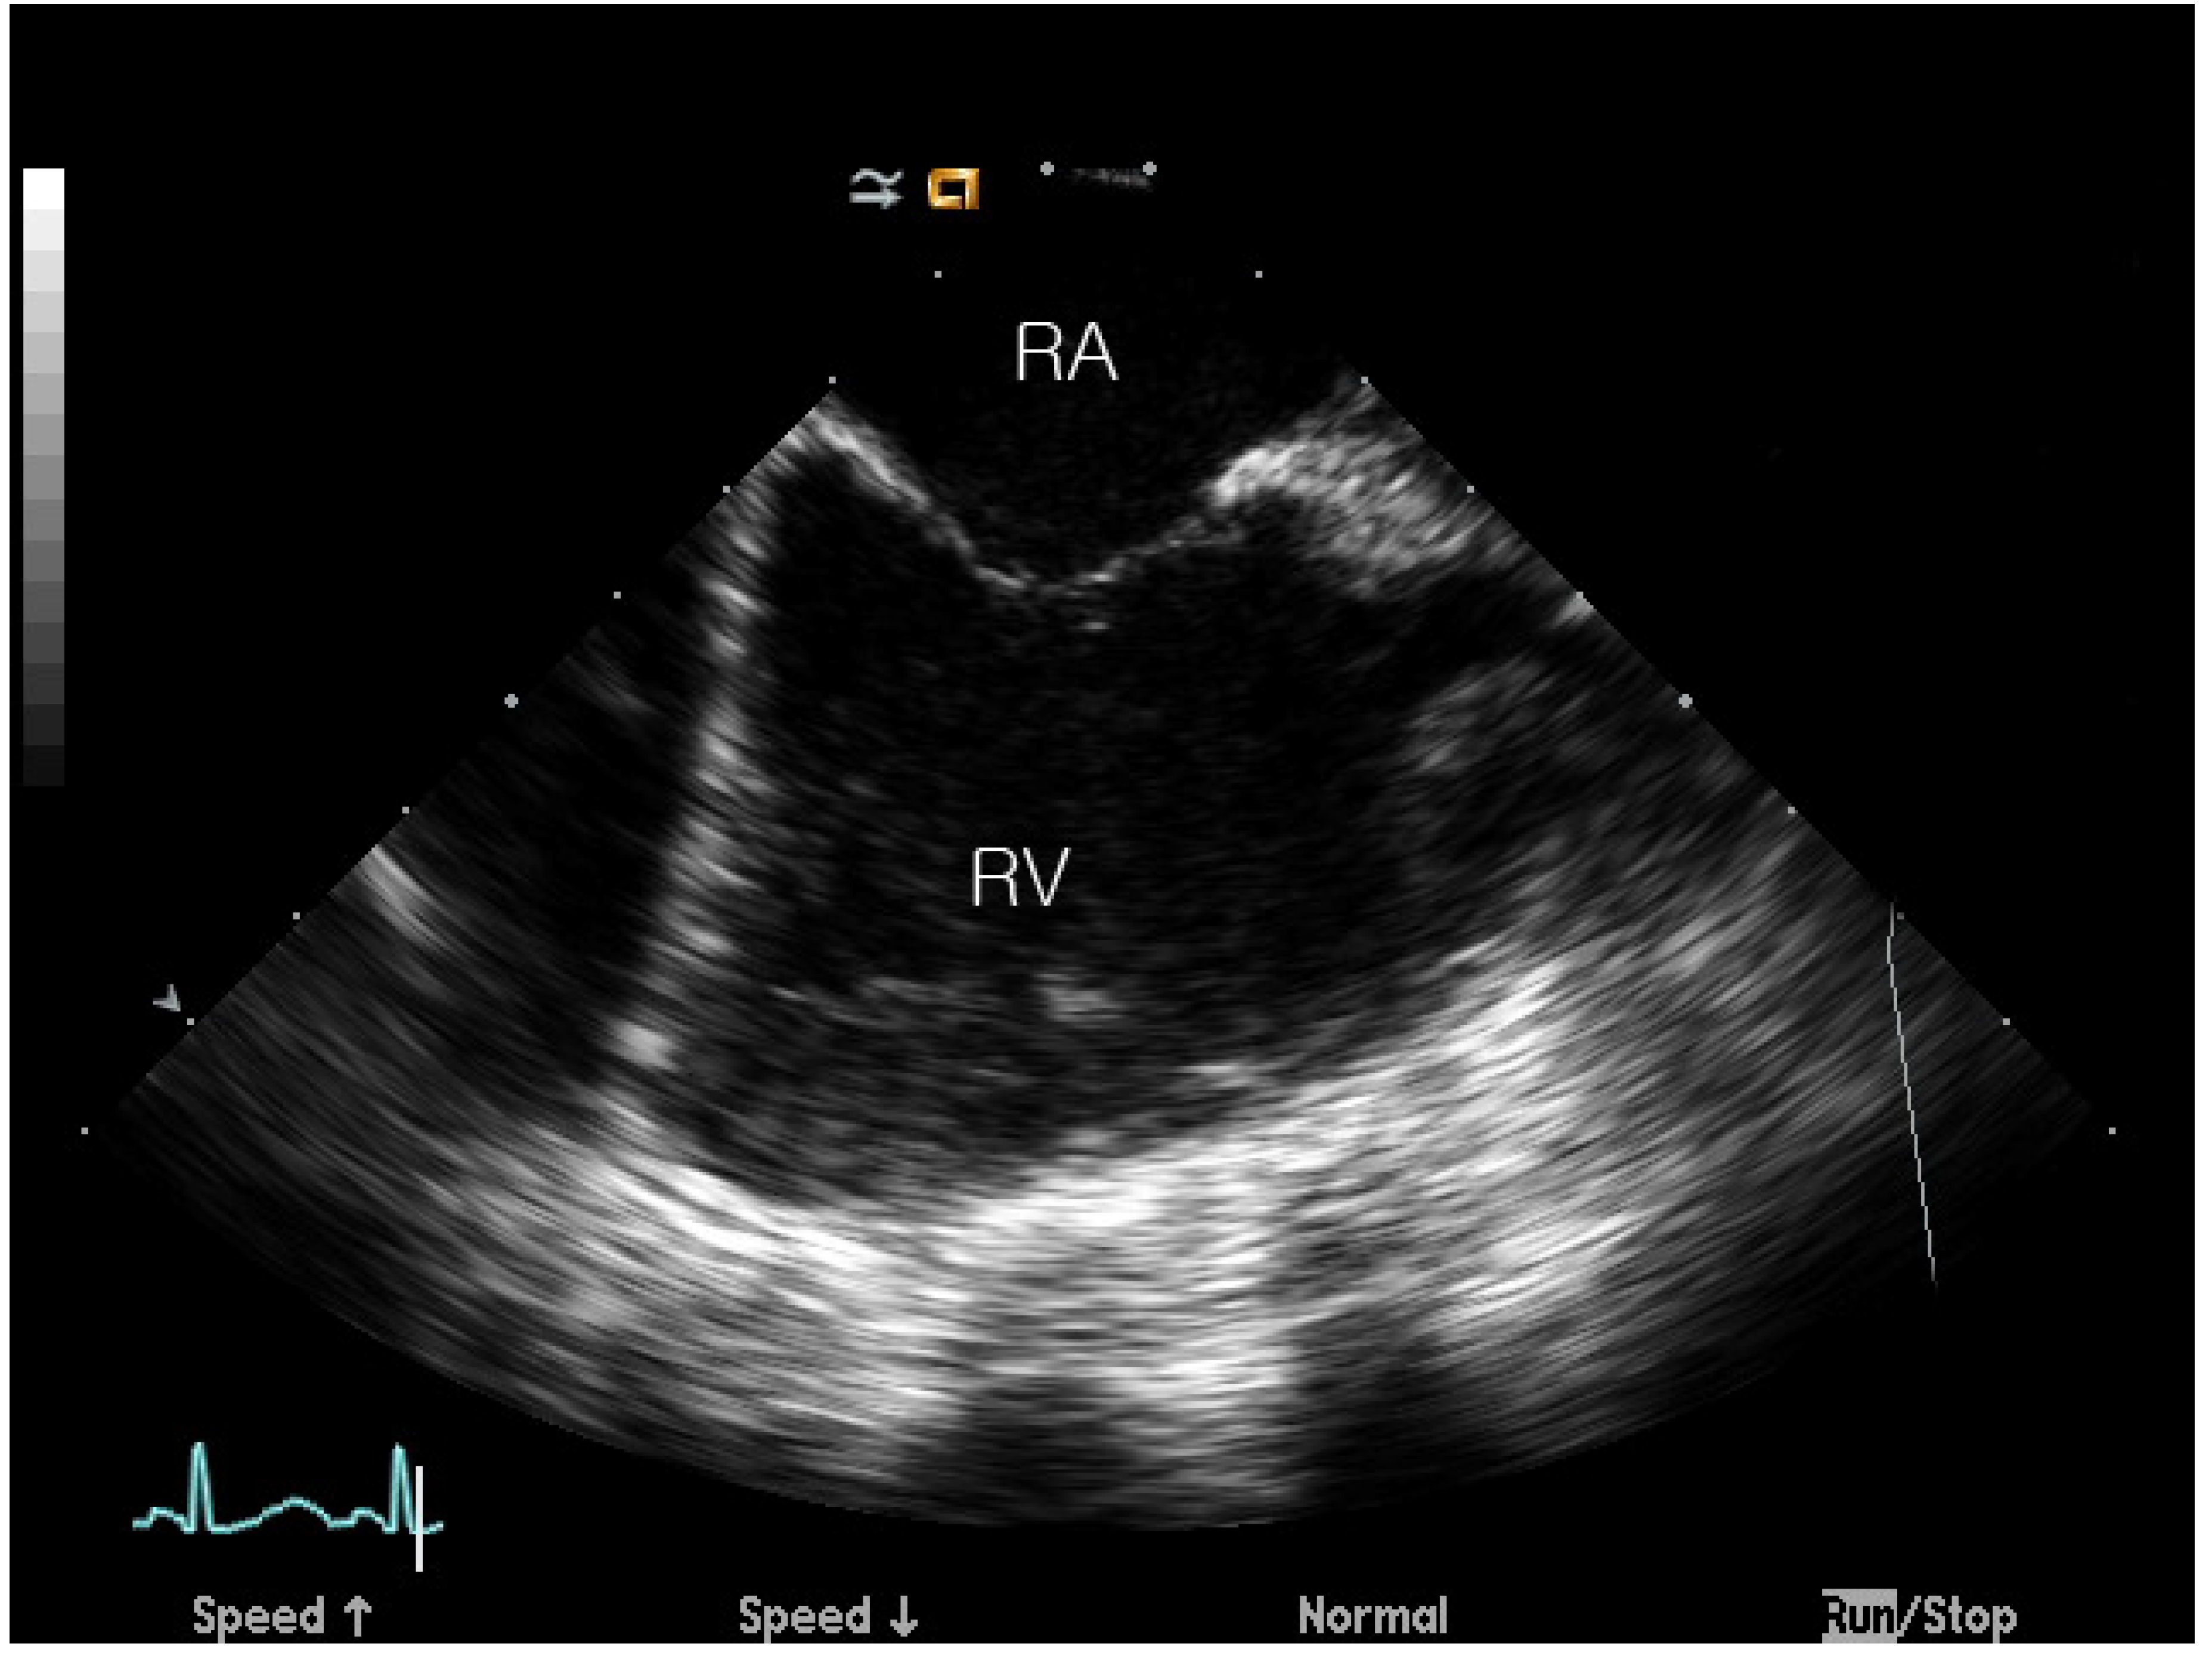

Velocity Vector Imaging Assessment of Functional Change in the Right Ventricle during Transcatheter Closure of Atrial Septal Defect by Intracardiac Echocardiography

2.2. ASD Device Closure and ICE Imaging Protocol